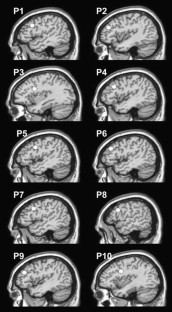

Fig. 1